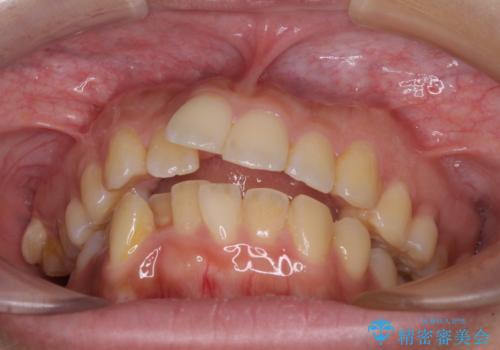

八重歯と上顎前突 ワイヤー装置での抜歯矯正

- 八重歯と、上下前歯が接触しないくらい前突した前歯を気にして来院された患者様です。

奥歯の噛み合わせは正常に近い状態でしたが、右上の奥歯に突起があったり、上下前歯が非接触であったりしていたため、補助装置を使用して上顎前歯を積極的に引っ込めるように計画しました。

口元の突出感を改善するために上下左右の小臼歯4本を抜歯し、ワイヤー装置によりデコボコを解消しながら口元の突出感も改善していくこととしました。